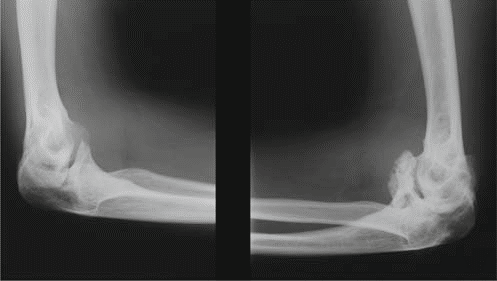

Additional Radiographs (Knees and Ankles):

To assess the widespread nature of MED, radiographs of other commonly affected joints were obtained.

* Knees: Revealed widened and irregular epiphyses of the distal femora and proximal tibiae. Patella alta was noted. Significant joint space narrowing was observed in the patellofemoral and medial tibiofemoral compartments. Mild valgus deformity was confirmed.

* Ankles: Demonstrated flattened and irregular talar domes, contributing to a widened ankle mortise and evidence of subtalar arthritis.

* This image typically represents an anteroposterior view of the knee, showcasing the irregular and flattened epiphyses, potentially widened and disorganized growth plates (if skeletally immature), and early degenerative joint changes consistent with the manifestations of Multiple Epiphyseal Dysplasia.